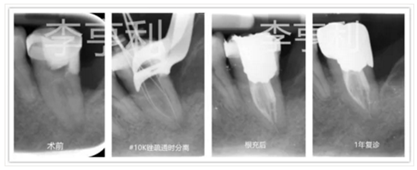

37術(shù)前診斷為無癥狀性根尖周炎,因轉(zhuǎn)診醫(yī)生在開髓時發(fā)現(xiàn)根管為C型,故轉(zhuǎn)至我處;在疏通根管時發(fā)現(xiàn)#10K銼分離,但未阻擋工作長度且顯微鏡下也無法暴露斷械,選擇進(jìn)行常規(guī)根管治療;1年后回訪發(fā)現(xiàn)根尖周暗影消失,37無任何臨床癥狀,根管治療判斷為成功

在各位根據(jù)上述有限的證據(jù)來作出臨床決定之前,請注意大部分的實驗都是來源于??圃\所或者是良好的學(xué)院配置,而我們也知道當(dāng)牙體牙髓治療的技術(shù)標(biāo)準(zhǔn)越高,根尖周炎癥對其療效的影響則越低 (Sj?gren et al.1990)。所以直接對治療產(chǎn)生影響的并不是分離器械的本身,而是由于其阻擋而影響的根尖段根管的消毒和充填。除此之外,還包括斷針發(fā)生在治療的哪個步驟;根管解剖;斷針位置和斷針類型 (Parashos & Messer 2006)。

由于根尖1/3是發(fā)生器械分離的最常見部位,嘗試直接取出的話容易過度損傷牙體組織,造成更復(fù)雜的醫(yī)源性錯誤,如臺階、偏移和側(cè)穿等,所以建立旁路才是應(yīng)該被視為首選方法 (Al-Fouzan 2003)。

最后,根據(jù)目前擁有的最高水平證據(jù),分離器械遺留于根管內(nèi)并不會對牙齒預(yù)后造成有統(tǒng)計學(xué)意義的影響,除非患牙有術(shù)前根尖周病損且又受到斷針阻擋無法進(jìn)行有效的根管消毒,治療效果才會受損 (Panitvisai et al.2010)。